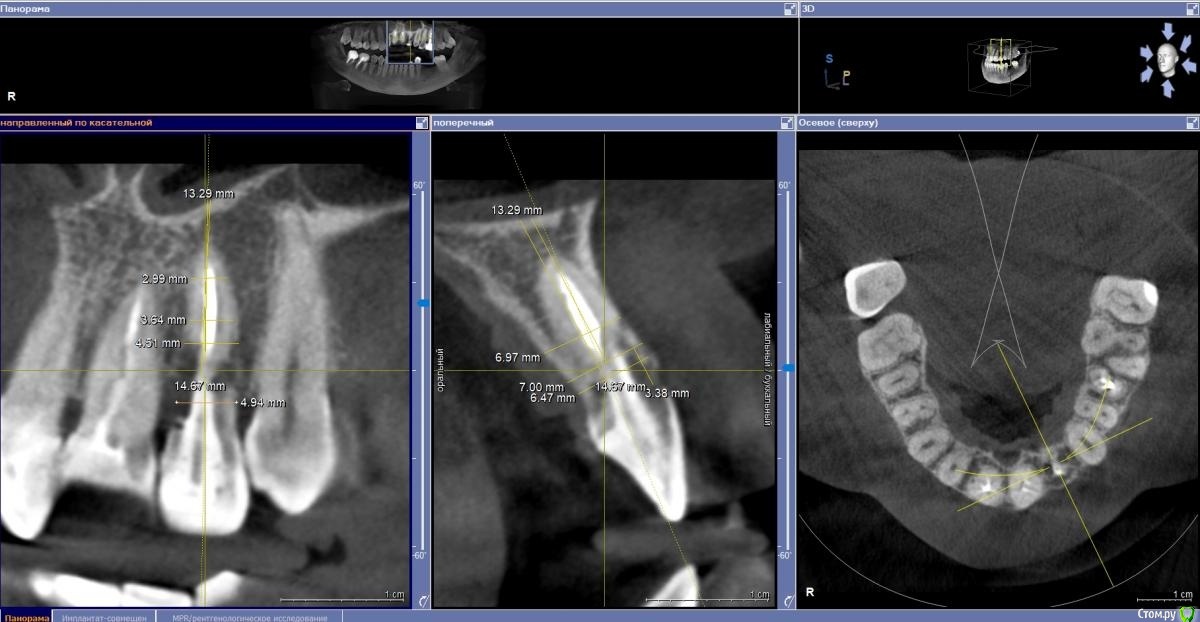

Fin Опубликовано 4 ноября, 2020 Поделиться Опубликовано 4 ноября, 2020 (изменено) Здравствуйте коллеги. В клинику обратилась пациентка с жалобой на эстетику передних зубов. В ходе осмотра и составления плана на КТ обнаружилась резка корня 22. Перфорация вестибулярной стенки на КТ не наблюдается. Думаю что при полном удалении корня вестибулярная стенка тоже уйдет. Техника IDR и B2S невозможна т.к. присутствуют восьмые зубы.Как вы считаете, стоит ли попытка сделать одномоментную имплантацию с техникой вариантов корневого щита или все таки идти на полное удаление? Изменено 4 ноября, 2020 пользователем Fin Ссылка на комментарий

Fin Опубликовано 9 ноября, 2020 Автор Поделиться Опубликовано 9 ноября, 2020 судя по снимку щит не получится, по причине его отсутствия Благодарю за ответ. Будем делать классику. А я думал наоборот пол дела сделано)) Х. Глюкман говорил что лучше немного подпилить корень в глубину, что бы не прорезался. Хотя тут не два мм а 4. Ссылка на комментарий

Fin Опубликовано 10 ноября, 2020 Автор Поделиться Опубликовано 10 ноября, 2020 (изменено) Нет тут места и на щит, и на имплантатНе понял Вас. Между корнями около 8 мм , 3.5 должен пройти. Больше беспокоит что после полного удаления корня образуется перфорация кортикальной стенки. Изменено 10 ноября, 2020 пользователем Fin Ссылка на комментарий

Fin Опубликовано 11 ноября, 2020 Автор Поделиться Опубликовано 11 ноября, 2020 (изменено) Нет тут никакого щитаПонял, стараемся максимально сохранить кортикалку при удалении Изменено 11 ноября, 2020 пользователем Fin Ссылка на комментарий